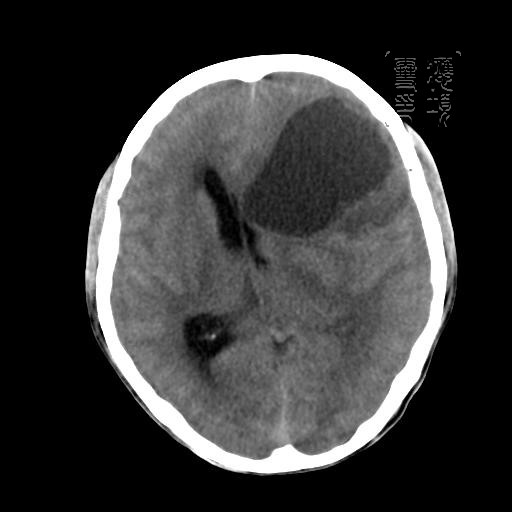

m 52y

二月前癫痫入院, 无既往史,现头痛、呕吐、视力减退、复视行ct平扫及增强检查。

左额叶囊实性占位,以囊性为主,并见明显强化不规则壁结节,占位效应明显,首先考虑是囊性星形细胞瘤.

从发病部位及年龄都不考虑是血管母细胞瘤,还有可能是胶质瘤.

可能为左额叶恶性胶质母细胞瘤。

胶质母细胞瘤的花边状强化及出血的特点这组片中没体现出来.还是支持囊性星型细胞瘤.